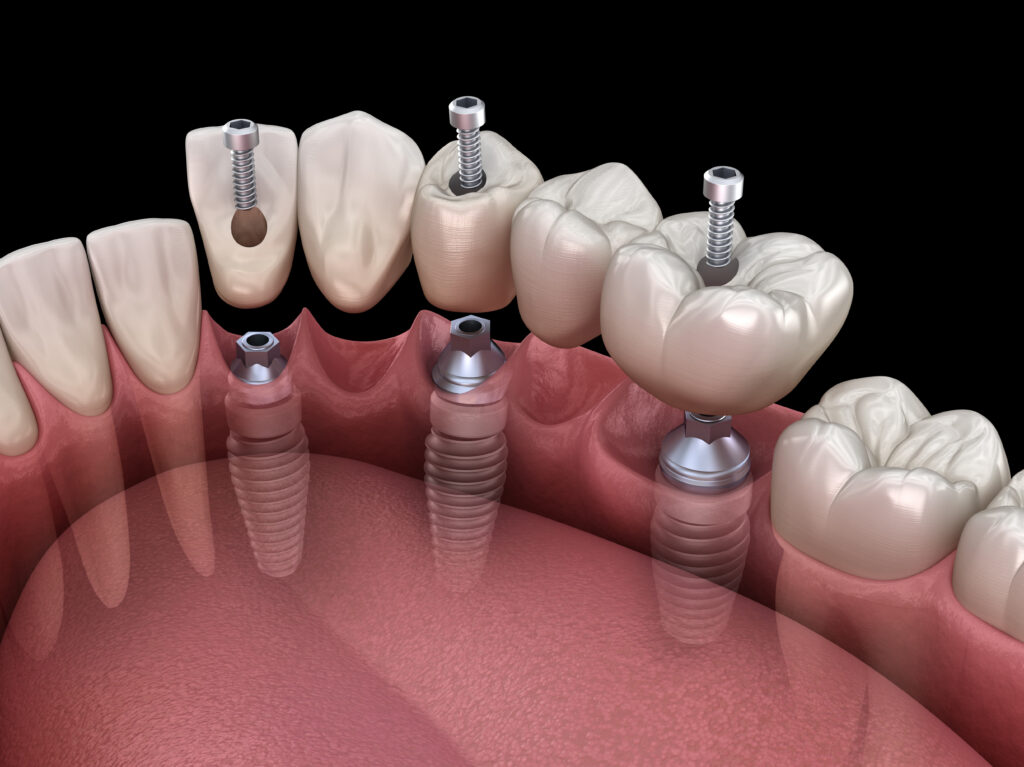

dental implant bridge photos Dental bridge bridges complete overview

Dental Bridges, A Complete Overview

www.infodentis.comdental bridge bridges complete overview

www.infodentis.comdental bridge bridges complete overview